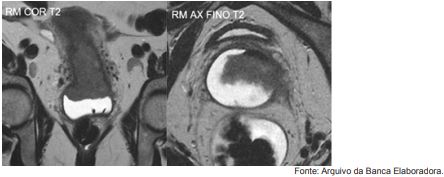

Paciente feminino, 38 anos, em estadiamento para neoplasia de colo uterino, realiza exame de ressonância magnética, conforme imagens abaixo (RM CORONAL T2 e RM AXIAL FINO T2).

À luz do quadro clínico, do exame de ressonância magnética e do sistema de estadiamento FIGO (International Feredation of Gynecology and Obstetrics) para a neoplasia de colo uterino, é correto afirmar que a/as